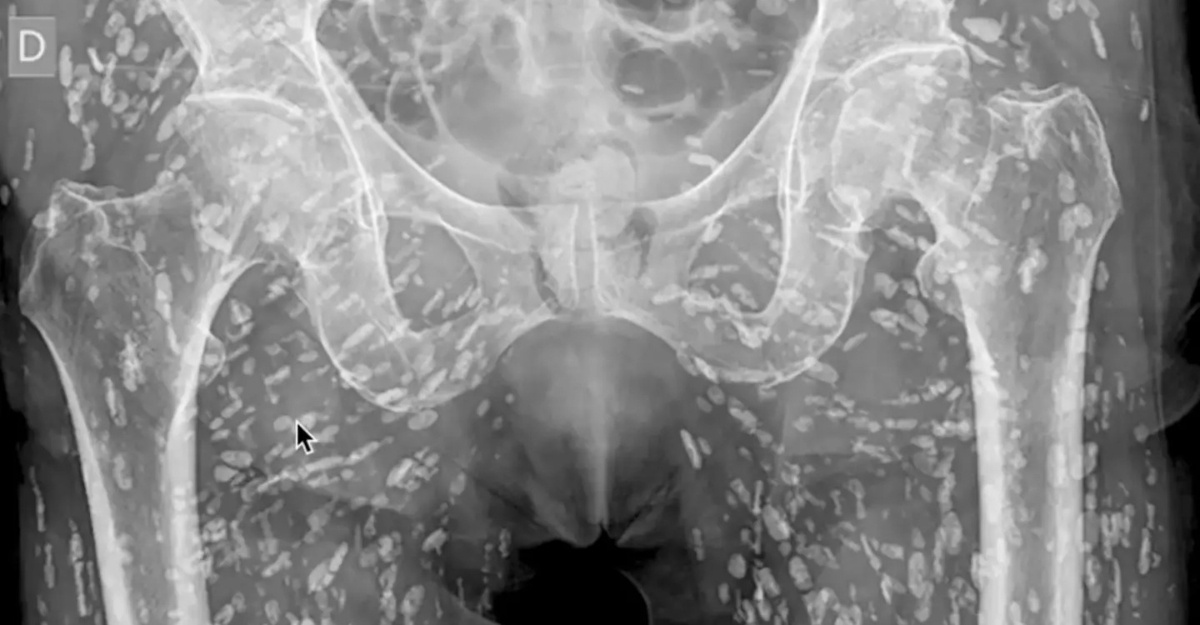

X-ray ratusan bintik putih

Sumber: X @EM_RESUS

Doktor Kongsi Imej X-Ray Tubuh Pesakit Dipenuhi Ratusan Bintik Putih

Seorang doktor yang pakar dalam radiologi kecemasan dan kardiovaskular mencuri perhatian ramai apabila memuat naik imej X-ray yang ‘mengejutkan’ di media sosial.

Imej X-ray tersebut memaparkan ratusan bintik putih di sekitar kawasan pelvis pesakit. Difahamkan, ia sebenarnya adalah telur cacing pita (tapeworms) yang telah terkalsifikasi di tisu lembut tubuh pesakit.

Pesakit tersebut hanya mengetahui keadaannya setelah menjalani X-ray akibat merasa sakit di bahagian pinggul selepas terjatuh.

“Ini adalah keadaan yang dikenali sebagai cysticercosis, di mana larva cacing pita taenia solium (cacing pita babi) membentuk sista (ketumbuhan) dalam badan,” jelas doktor tersebut.